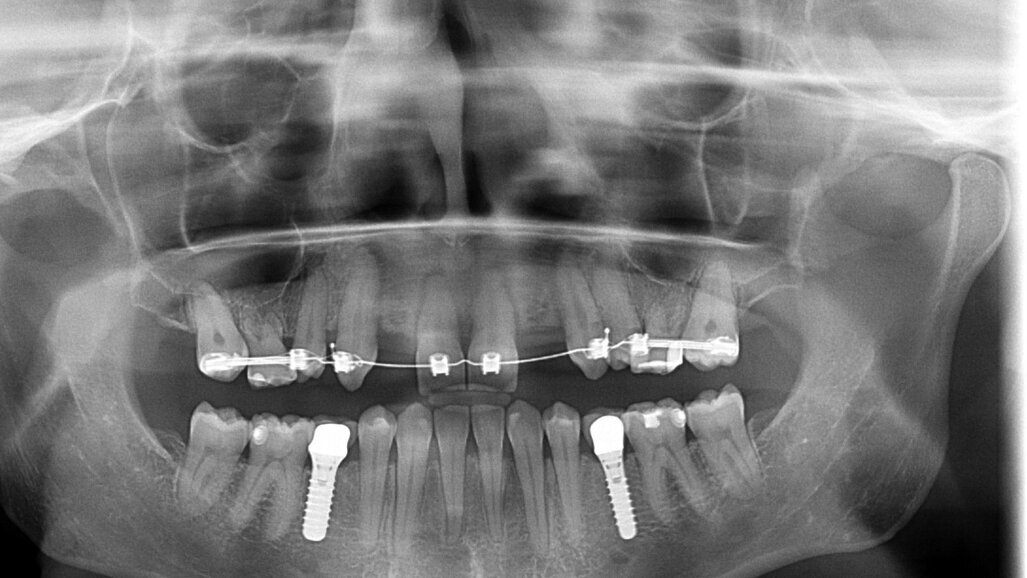

In samenspraak met de patiënte en in goed overleg met de behandelend orthodontist werd besloten de implantaten op de posities 13 en 23 te verwijderen, de cuspidaten naar distaal te verplaatsen en de angulatie van de elementen te corrigeren, zodat het plaatsen van twee implantaten op de posities van de laterale incisieven goed mogelijk zou worden (afbeelding 5 en 6).

Door de regulatie van de cuspidaten naar distaal is botappositie opgetreden, waardoor bij het plaatsen van de twee implantaten een minimale botopbouw volgens een GBR-techniek noodzakelijk was (afbeelding 7-9). Via digital smile design werd de uiteindelijke vorm gesimuleerd (afbeelding 10 en 11). Er werden twee verschroefde zirkonium kronen met opgebakken porselein vervaardigd voor de implantaten en er werden facings van lithiumdisilicaat gemaakt bij de centrale incisieven en cuspidaten (afbeelding 12-17).